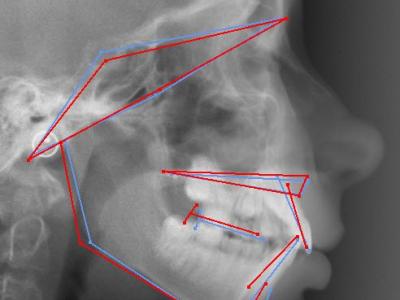

Vues endo-buccales (a, b, c) et téléradiographie de profil initiales avec IMPA=105° (d);

vue endo-buccales (e, f, g) et téléradiographie de profil (h) à 1 an post-opératoire (sans traitement orthodontique) montrant un redressement spontané des incisives mandibulaires avec IMPA=94° et une avancée du point B ;

superposition avec le logiciel Procuste (Rouge = Avant / Bleu = Après) montrant le repositionnement incisif et la croissance mandibulaire (i) ;

vue endo-buccales (j, k, l) et téléradiographie de profil (m) à 4 ans post-opératoires, avec traitement orthodontique multi-attaches et 1 an de contention, l’IMPA est resté stable à 94°.

Téléradiographie de profil initiale, IMPA = 108° (a),

à 11 mois post-opératoires avec 8 mois de nivellement sur arc rond, les incisives mandibulaires se redressent spontanément de 11° (IMPA = 97°) et la concavité de la symphyse diminue significativement (b),

superposition avec le logiciel Procuste (Rouge = Avant / Bleu = Après) (c).

Téléradiographie de profil avant traitement (a),

téléradiographie de profil de réévaluation à 12 mois de traitement multi-attaches montrant l’aggravation de la proalvéolie mandibulaire avec IMPA=110° (b), l’affaiblissement labio-mentonnier est décidé à ce moment,

téléradiographie de profil en fin de traitement après 9 mois de finitions sur multi-attaches et 1 an de contention, l’IMPA est réduit à 100° et le muscle mentonnier s’est relâché (c),

superposition avec le logiciel Procuste (Rouge = Avant / Bleu = Après) montrant le redressement radiculaire des incisives mandibulaires et la croissance mandibulaire (d)